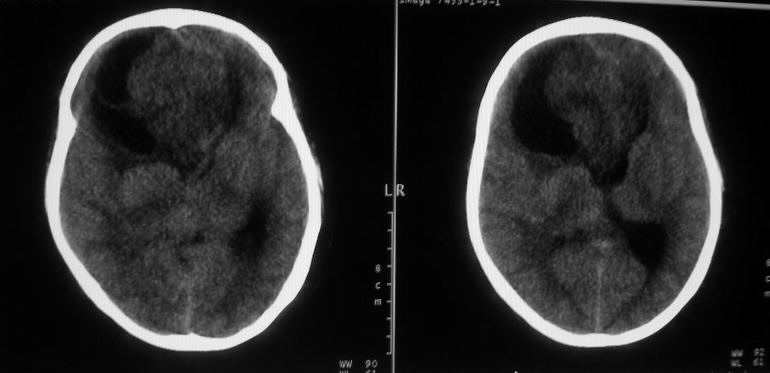

标题: CT18148:女,44岁,头痛数月。 [打印本页]

女,44岁,头痛数月。

右侧额叶占位性病变,考虑脑肿瘤;建议行进一步检查。

右侧额叶占位性病变,考虑脑膜瘤可能性大;建议行进一步检查。